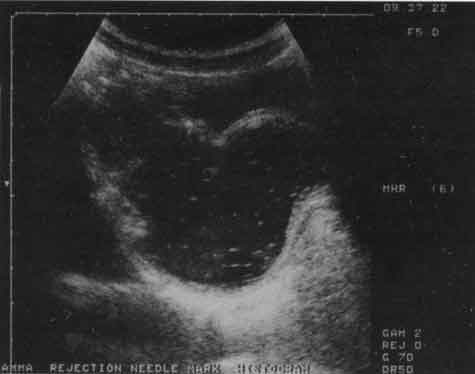

Диагностика болезни Гиршпрунга и долихосигмы сходна с рентгенологической. В первом случае определяется значительное расширение кишки (воронка) выше ее суженного отдела, имеющего выраженное утолщение стенок. Во втором обнаруживается одна или несколько дополнительных петель сигмовидной кишки, как правило, с нормальными стенками. Преимущество в этих случаях УЗИ перед рентгенографией состоит в его значительно большей доступности, простоте применения, отсутствии ионизирующей радиации. Вместе с тем метод эхографии является как бы дополнительным, скрининговым методом, на основании результатов которого решаются вопросы дальнейшей диагностической и/или лечебной тактики для конкретного ребенка (рис. 11).

Рис. 11. Эхограмма прямой (R) и сигмовидной (S) кишки при болезни Гиршпрунга.